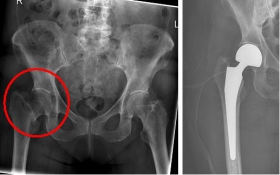

In older age and with stronger displacement of the fracture can be done by a duo-head prosthesis. Here only the femoral head is replaced, the hip socket is preserved. In case of simultaneous hip arthrosis, a total endoprosthesis (hip replacement) with replacement of the acetabular cup can be used.

Picture: This picture shows the treatment of a severely displaced fracture with a so-called duo head prosthesis. The acetabulum was left here.